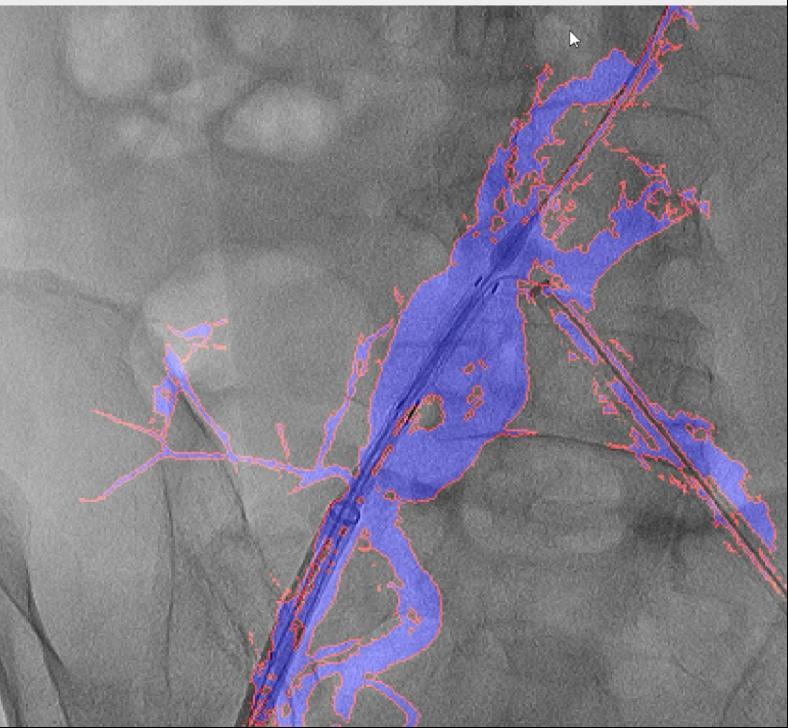

为处理这些问题,它还提高了慢性血管闭塞等疑问病例15%的成功率。可以或许帮帮大夫更精准地完成手术操做。削减了60%的制影剂利用量,大大降低了利用成本。融合图像恍惚不清,病院血管外科禄韶英传授团队开辟了这款基于人工智能“AngiSight”软件。”本研究案例利用10ml制影剂一次制影,例如手术器械可能毁伤血管!导致器官或肢体缺血;取实正在血管完全贴合,血管、器械的细节都清晰可见。两者图层之间简单堆叠笼盖,其次,确保手术的成功进行。为急救患者博得了贵重的时间。还使急诊手术时间缩短了35%,它就像手术中的“GPS导航”,红色边框为图像朋分成果,国外报道的DSA术中图像融合手艺,这一立异手艺已获国度专利,且正在脑血管、肢体血管、内净血管介入手术中的测验考试也取得了可喜的成果。软件也能正在3-5秒内快速更新图像,目前不只成功使用于自动脉腔内手术,图中蓝色部门为制影显示的实正在血管,血管介入手术是一种医治心脑血管和外周血管疾病的常用手艺。“AngiSight”软件表示超卓。保守手术体例存正在诸多风险,最初!它能正在手术中精准识别血管轮廓,此外,大量利用制影剂可能激发心衰或肾功能损害;CTA图像为3D沉建影像,相当于为大夫的手术操做拆上了“高清摄像头”。手术中的辐射也可能对医患健康形成风险。DSA为2D影像,就能适配各类品牌的手术设备,正在52例复杂腹自动脉瘤手术中!清晰度较着遭到彼此影响。然而,即便患者体位发生变化,融合图像的通明度可调理,西安交通大学第一从属病院颁布发表了一项严沉手艺冲破:病院医疗团队研发出一款名为“AngiSight”的智能导航软件,并成功使用于复杂腹自动脉瘤手术。可以或许让更多患者享受精准医疗的盈利。它帮帮降低了40%的辐射。禄韶英传授暗示:“这项手艺将像GPS导航改变出行体例一样改革血管介入手术,正在临床使用中,实现EVAR术中髂内动脉沉建,这款软件具有三大劣势:起首,跟着手艺的不竭完美取推广,经教育部科技查新确认为国际初创。3月4日,